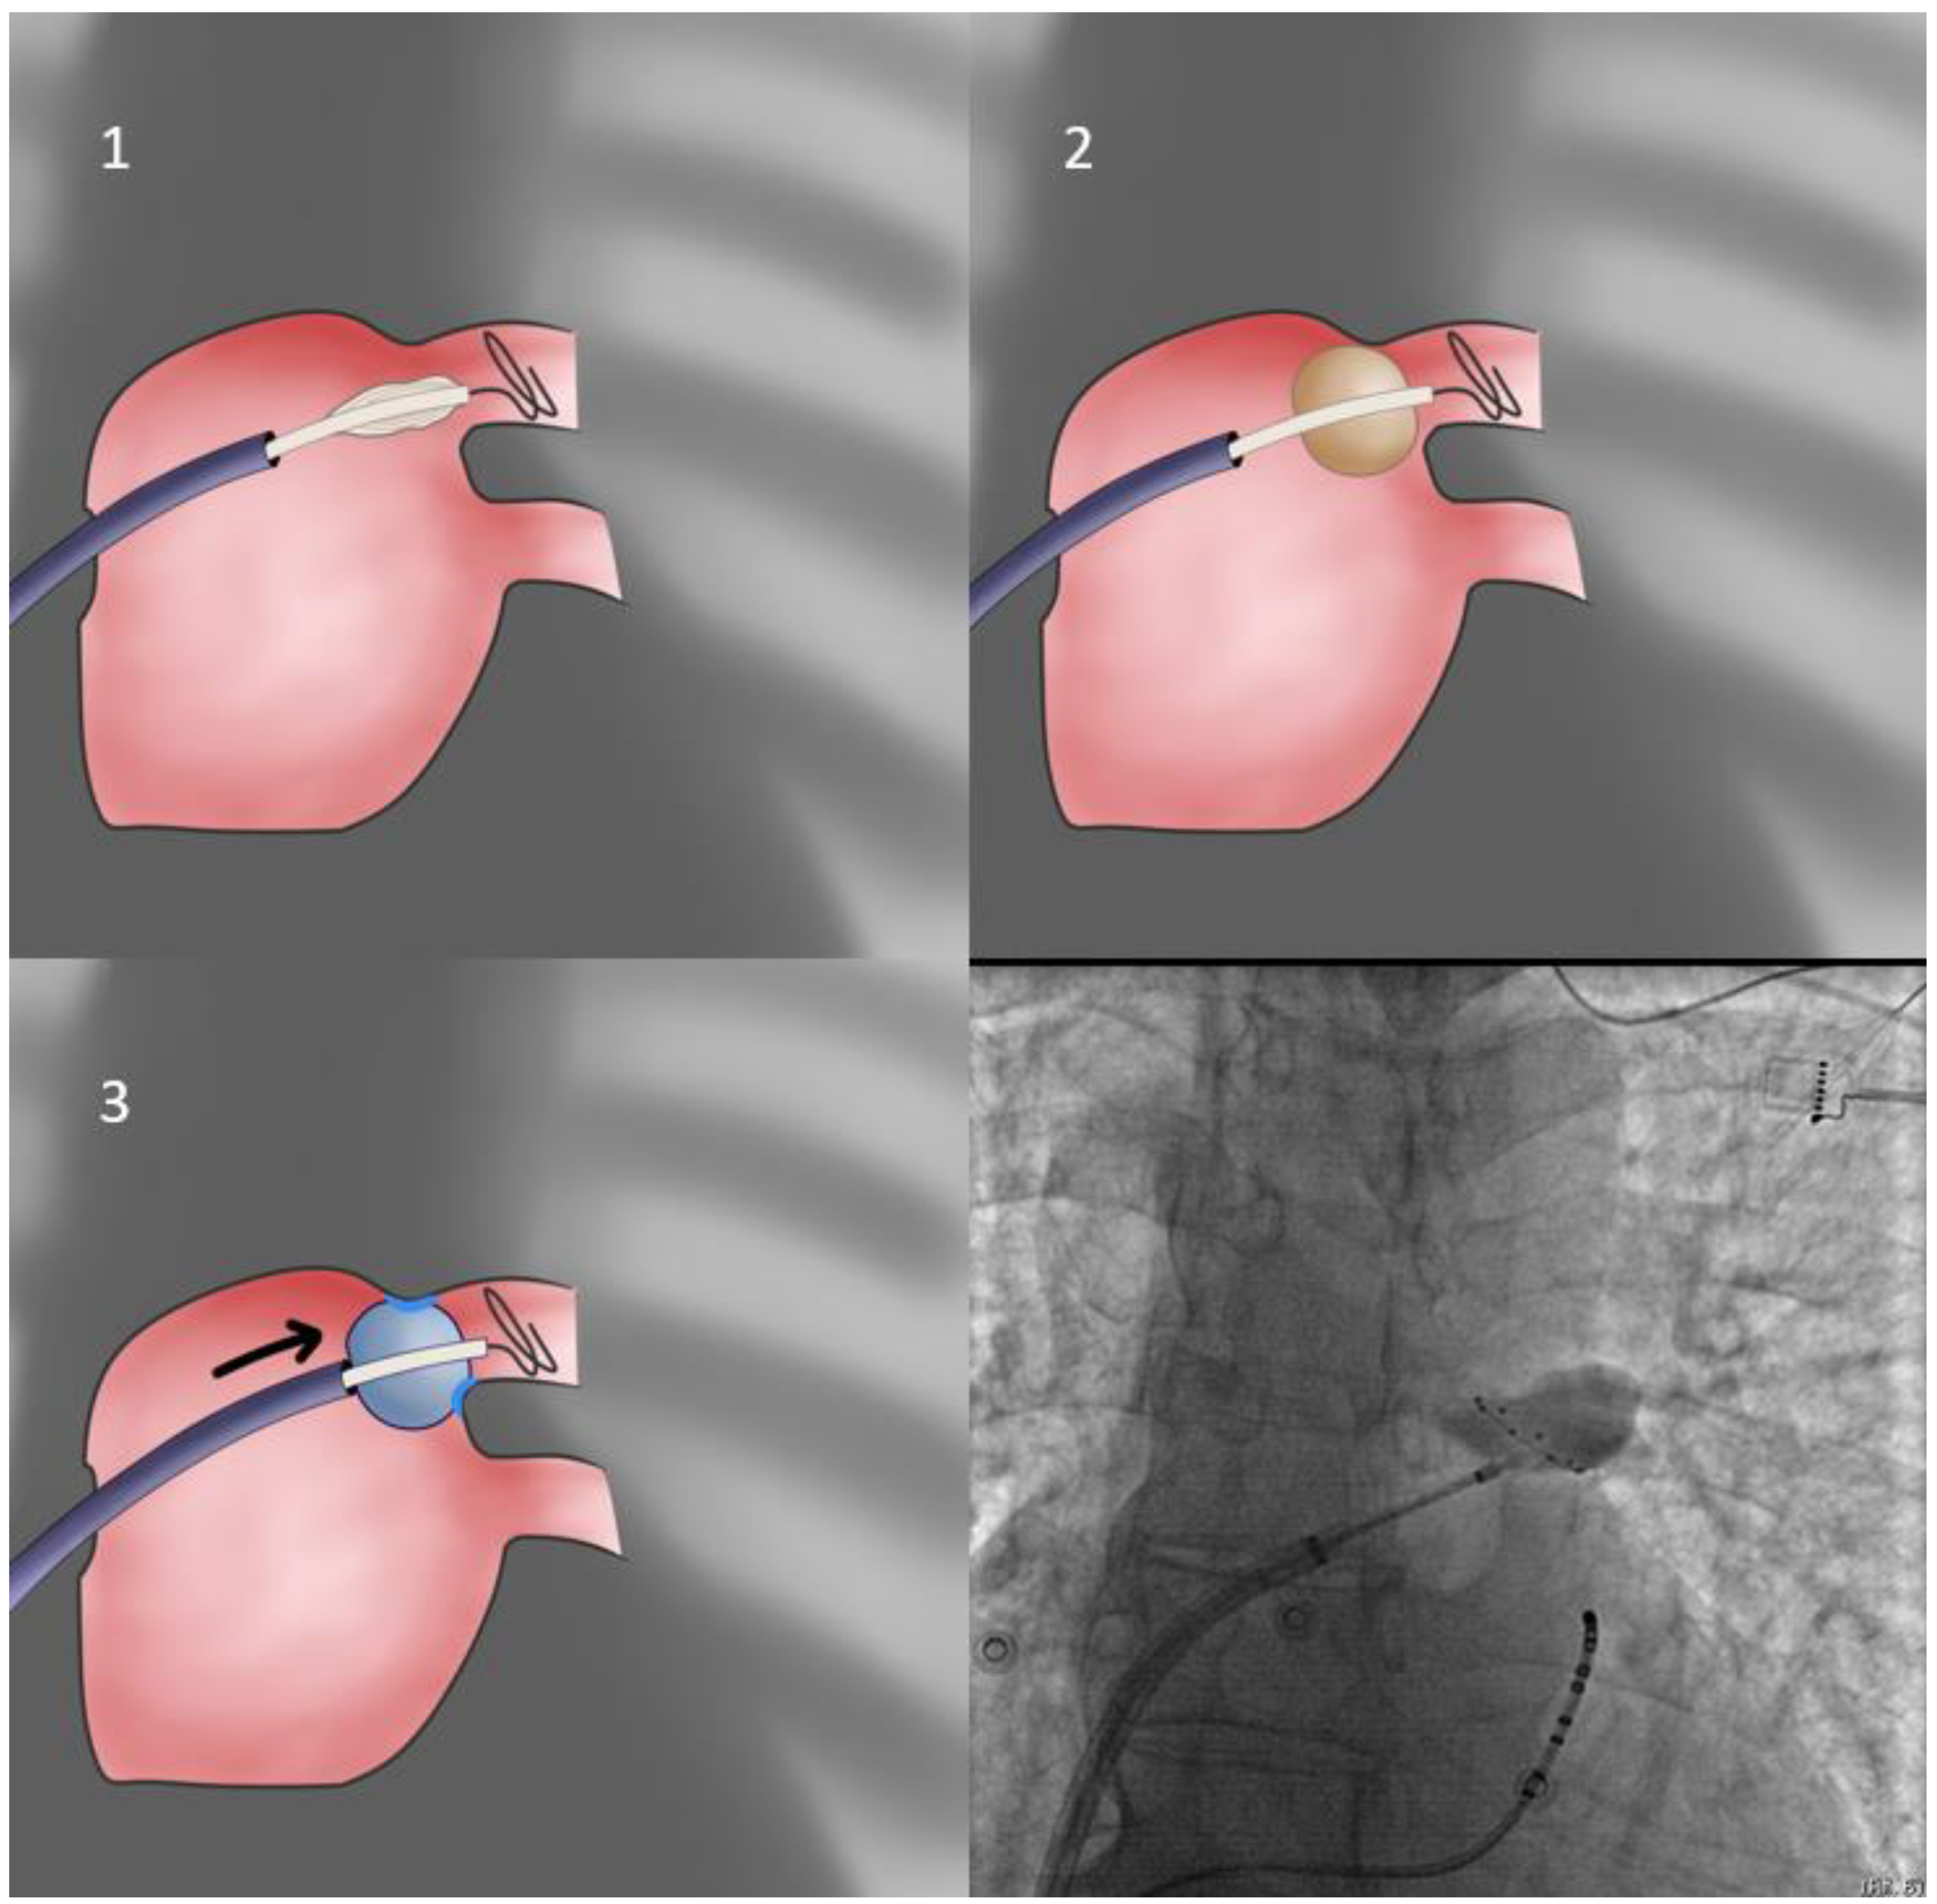

- Our first approach is using the sheath as the support for PV sealing (FlexCath based direct approach—Figure 1). With the whole system (Achieve catheter, cryoballoon and sheath) in contact and the sheath slightly flexed, we aim to align its distal part with the axis of the balloon and the Achieve catheter. Given that a vein may change the orientation of its course very near its antrum, it is the proximal part of the Achieve catheter that should be used for defining proper system alignment [53].